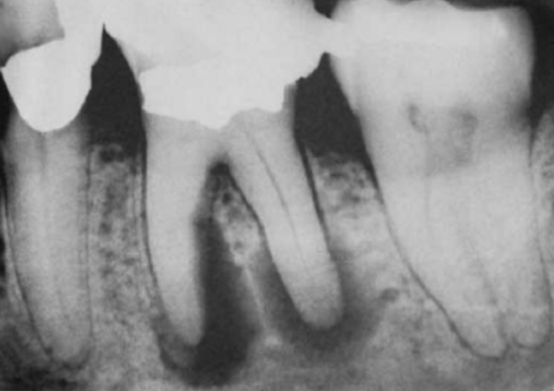

根尖片上显示严重的根尖周炎,可能导致牙齿无法保留